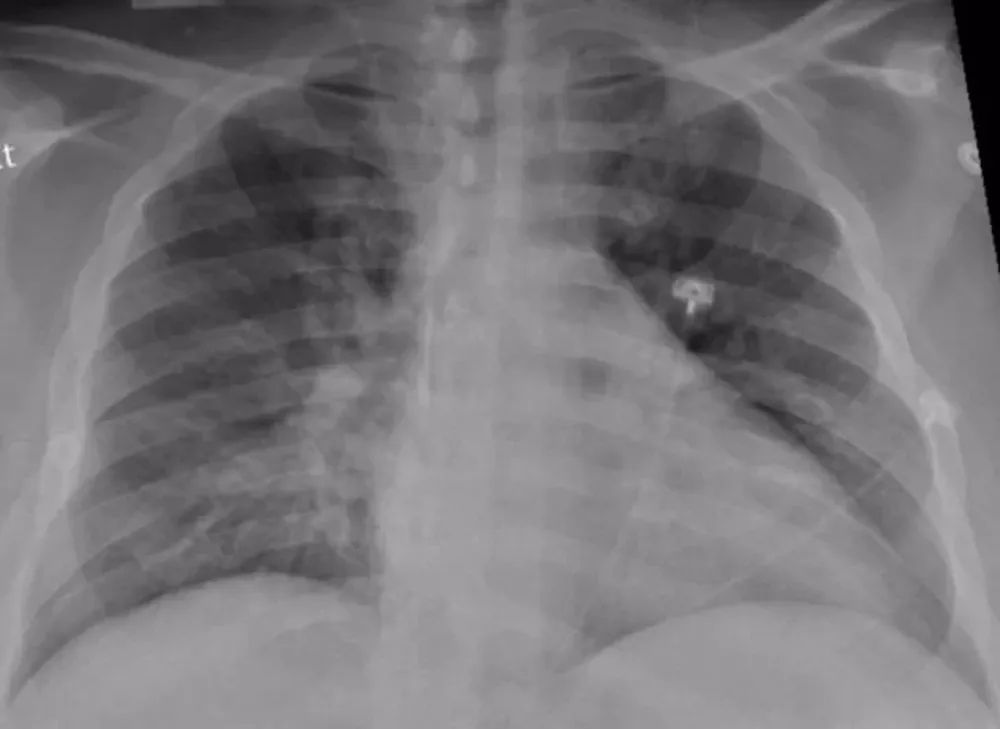

La neumonía es la principal causa de mortalidad por infección a nivel mundial y se ubica entre las 8 causas de muerte más comunes en adultos (2019), junto a la enfermedad pulmonar obstructiva crónica (EPOC) y el cáncer de pulmón. Además, según datos del estudio Global Burden of Disease, solo en 2019 fallecieron por neumonía más de 700.000 niños y un millón de personas mayores. ¿Qué debemos saber y cómo podemos prevenirla?

Los síntomas incluyen el aumento de producción de moco, fiebre, dolor torácico, dificultad respiratoria o falta de aire y dolor en puntada de costado. Si la persona presenta estos síntomas debe acudir a su médico para un diagnóstico certero y así poder acceder precozmente a un tratamiento adecuado.

El tratamiento para la neumonía implica la cura de la infección y la prevención de sus complicaciones. La mayoría de las personas que presentan neumonía adquirida en la comunidad (NAC) pueden recibir tratamiento en sus hogares. El médico decidirá el tratamiento específico, que dependerá del paciente (edad, antecedentes, etc.), y de la gravedad del cuadro clínico.

En Argentina la neumonía es la 6ª causa de muerte en general y la 5ª causa en mayores de 60 años. Además, la presencia de enfermedades cardiovasculares y de otras enfermedades aumenta el riesgo de sufrir formas graves. Se sabe que la vacunación, el diagnóstico precoz y el tratamiento también precoz con los antibióticos adecuados disminuyen el riesgo de morir por esta infección.